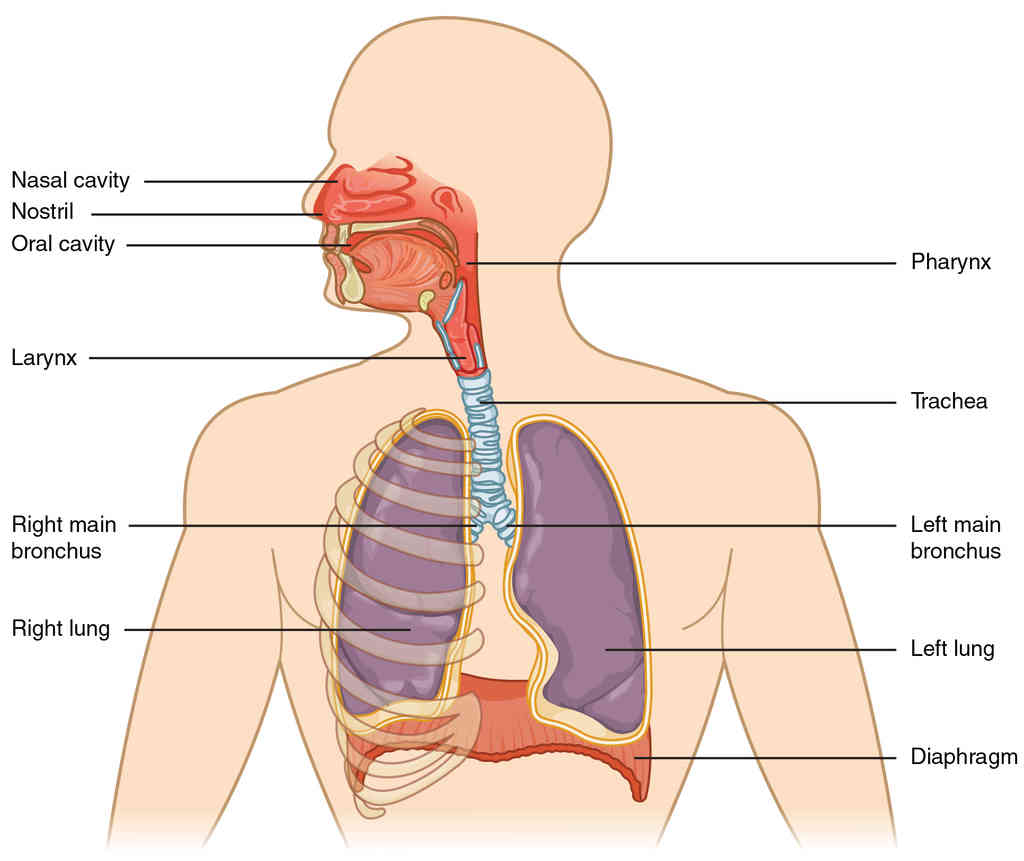

This page is under construction. For now, it is just a resource of the images found in the OpenStax Anatomy and Physiology Handbook. It wil slowly change into a revision tool. Each slide has a number. Use this to refer to the slide. When completed, it will have an unlabelled section, with labelled slides in parallel. On the unlabelled slides, write your answer and use the labelled slide to assess yourself. Keep track by also noting the number on each slide. Improvement at each attempt is important, more so than full marks on a first attempt.